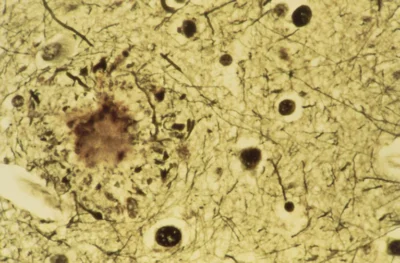

(Alzheimer-Immagine: le persone con malattia di Alzheimer di solito sviluppano placche proteiche (macchia circolare a sinistra) nel cervello. Credito: Biblioteca fotografica scientifica).

Sviluppato da Eisai, una società farmaceutica di Tokyo, e dalla società di biotecnologie Biogen di Cambridge, Massachusetts, Lecanemab è un anticorpo monoclonale progettato per eliminare i grumi di proteine dal cervello che molti ritengono essere la causa principale del morbo di Alzheimer. Questa teoria, nota come “ipotesi amiloide”, sostiene che la proteina amiloide-β si accumula in depositi tossici con il progredire della malattia, causando infine la demenza.